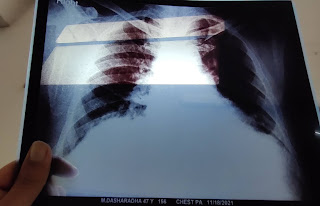

Ultrasound